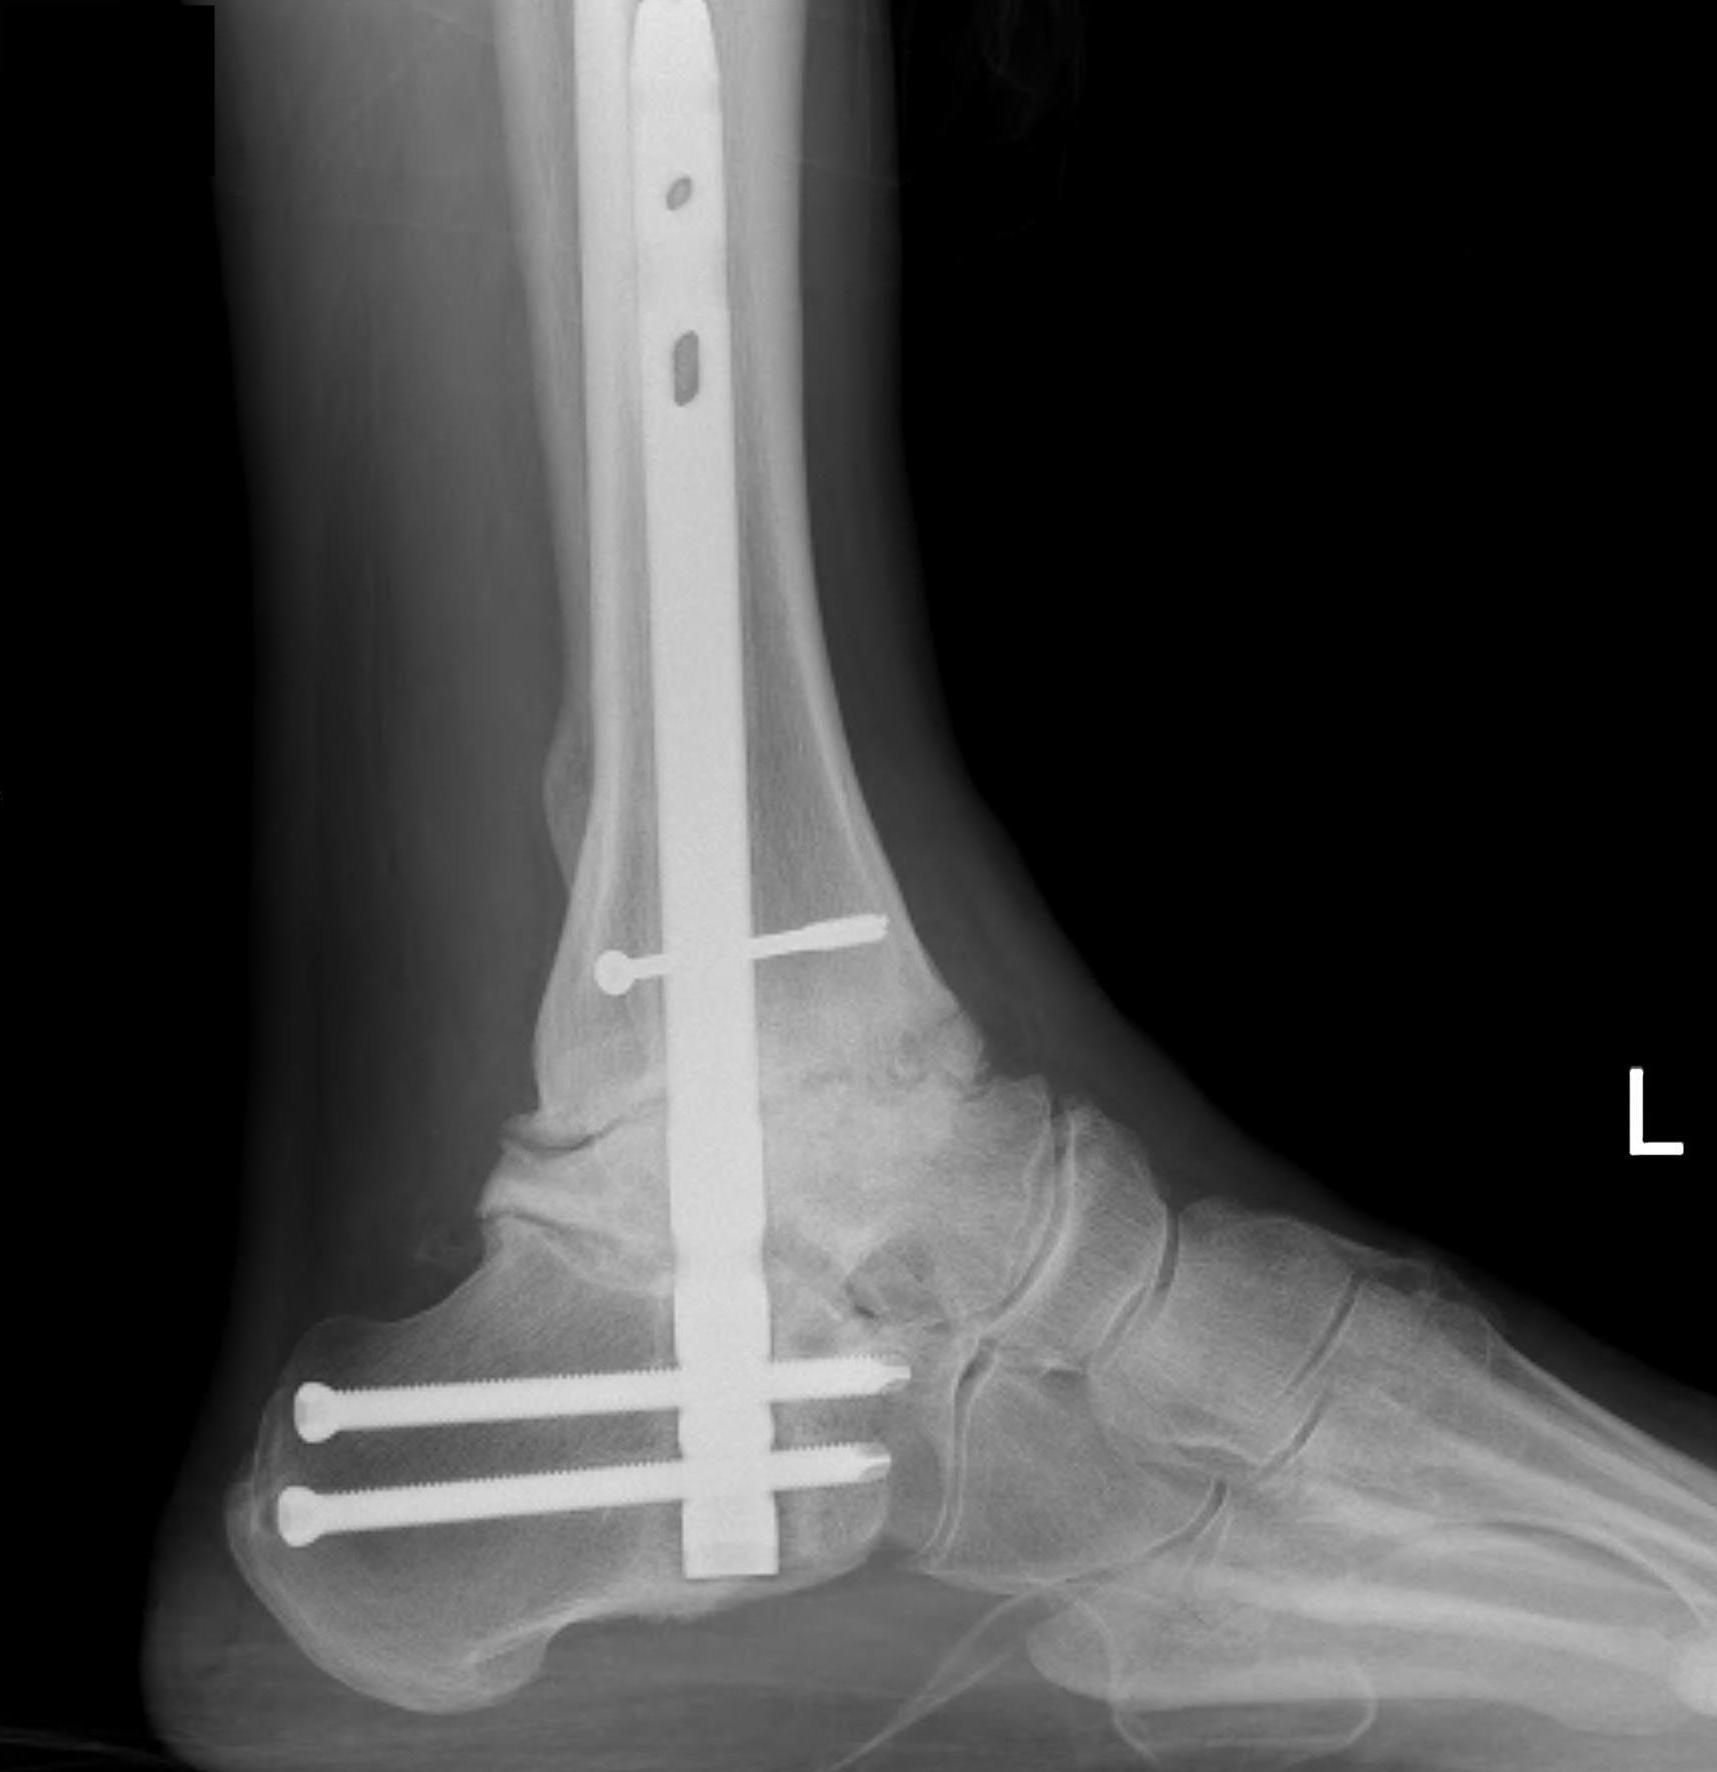

Pantalar fusion with hindfoot nail

talus avntalus AVNPantalar fusion